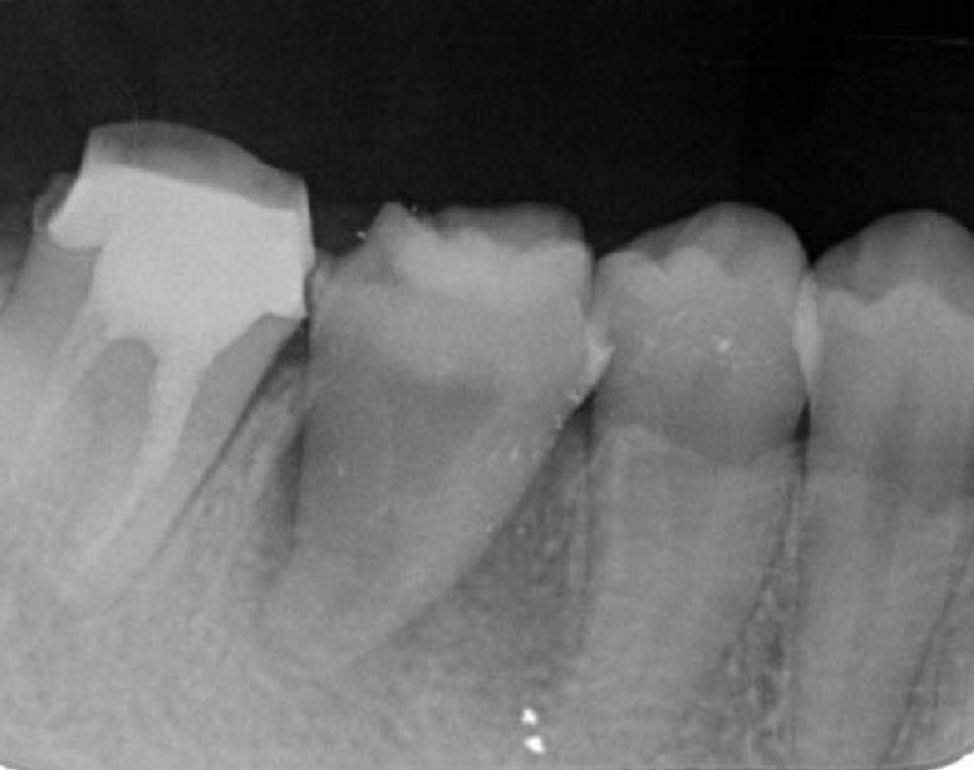

A 27-year-old female patient came to us with discomfort in the right lower jaw (Figure 1). Her primary symptoms were pain in the lower right tooth when biting and discomfort associated with not being able to chew well with the lower left single denture. The patient was married and had one young child, and previously received dental treatment in China, then had returned to Japan for childbirth and early childcare. The patient was a nonsmoker with moderate plaque control and medical history taking revealed no problems. In clinical and radiographic examinations, a root fracture was observed on tooth #46, which had been endodontic ally treated and restored with a full-cast metal crown. Periodontal probing revealed a pocket depth of 8 mm on the buccal center side of the tooth. No pain was detected with percussion and mobility of the tooth was normal. (Figure 1, Figure 2, Figure 3).

Figure 2.Pre-treatment X-ray findings. A cystic lesion was found in the mesial and distal roots apex, and root nodule of #46.